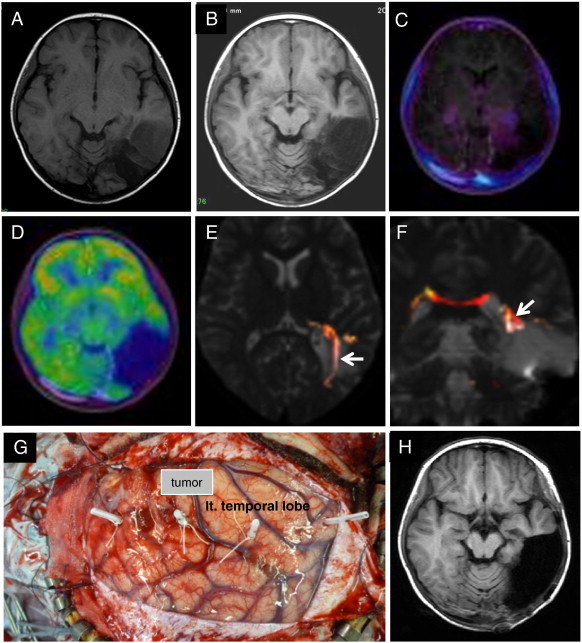

Fig. 6.

Case 3. T1WI after the first surgery showing a partially resected, well-demarcated, hypointensity mass lesion in the left posterior temporal lobe (A). Two years later, T1WI showing tumor progression (B). The tumor showed low uptake in MET-PET (fused with T1WI) (C) and hypo-uptake in FDG-PET (fused with T1WI) (D). Fiber tractography showed the left visual tract (arrow) to be mediorostral to the tumor (E and F). This is a photograph showing the neuronavigation-guided fence-post tube technique used in the surgery (G). Postoperative T1WI showed that the tumor was totally resected (H).